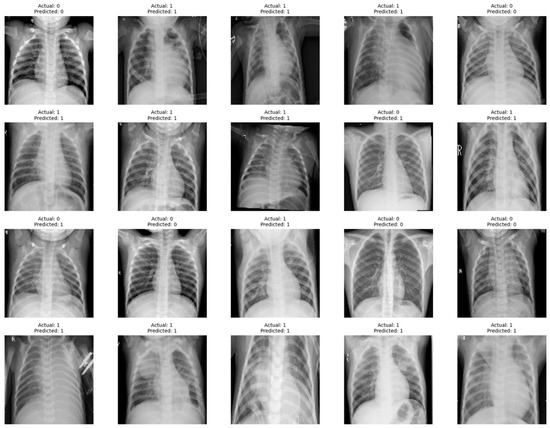

- Insight into Class Imbalances: In situations where there is a class imbalance (significant difference in the number of instances between classes), a confusion matrix helps identify how well the model performs for each class.

- Model Comparison: When comparing multiple models, a confusion matrix facilitates a side-by-side evaluation of their performance, enabling stakeholders to make informed decisions about which model is better suited for a particular task.

- Diagnostic Information: The confusion matrix is particularly useful in medical and diagnostic applications, providing information on the model’s ability to correctly identify positive (disease presence) and negative (disease absence) cases.